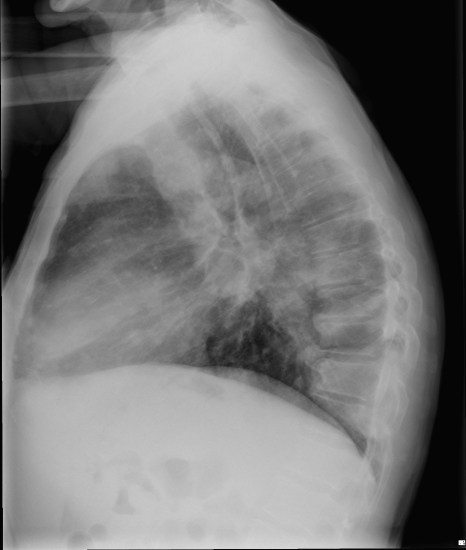

CASO: Febrícula y tos de 4 días de evolución.

Hallazgos:

- En la placa PA se observa una asimetría en los hilios pulmonares, el hilio izquierdo tiene una densidad aumentada.

- Tras examinar la placa lateral se observa un aumento de densidad en la columna que puede ser compatible con una condensación, es el signo de la desnificación vertebral.

SIGNO DE LA DENSIFICACIÓN VERTEBRAL: En la radiografía lateral normal, la densidad de la columna torácica tiende a disminuir desde la parte superior hasta el diafragma; la alteración de ese patrón por la presencia de una densidad superpuesta a la columna, indica la existencia de una consolidación pulmonar. Este signo adquiere especial valor cuando en la proyección posteroanterior la consolidación está oculta en el espacio retrocardíaco o en la base pulmonar.